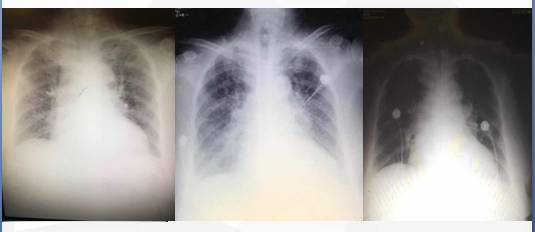

治疗后胸片